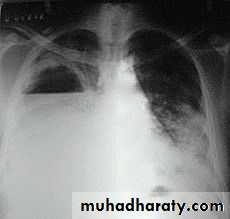

Patient with fever, rigor and dyspnea